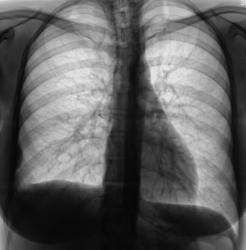

Пол пациента: Мужской пол Тип патологии: Злокачественное новообразование Область исследования: Грудная клетка и верхние дыхательные пути Методы исследования: Rg Сегодня, при расшифровке флюорограмм, пациента "взяли на контроль". Заподозрили наличие мезотелиомы. Ваше мнение коллеги? 1.MEZO_..jpg 2.MEZO_..JPG 3.MEZO_..jpg ВложениеРазмер 1.MEZO_..jpg73.66 КБ 2.MEZO_..JPG55.21 КБ 3.MEZO_..jpg59.52 КБ Ср, 02/12/2009 - 09:16 #1 Almo Не на сайте Был на сайте: 1 неделя 5 дней назад Зарегистрирован: 28.09.2008 - 18:50 Публикации: 8302 Да, похоже на мезотелиому.Рёбернодиафрагмальный синус затенён нет ли там выпота? Ср, 02/12/2009 - 19:38 #2 Глазков Игорь А... Не на сайте Был на сайте: 1 год 2 месяцев назад Зарегистрирован: 19.12.2008 - 20:41 Публикации: 1597 здесь травмы? Купол диафрагмы уплощён, синус практически не определяется, осумкованный выпот паракостально? Укладка ровная, но тень средостения смещена влево. Прийди к Себе Ср, 02/12/2009 - 21:59 #3 Анатолий Владим... Не на сайте Был на сайте: 8 лет 2 месяцев назад Зарегистрирован: 16.10.2009 - 21:16 Публикации: 1941 Необходимы повторные снимки с четким отображением структуры ребер - патология может быть там. Ср, 02/12/2009 - 22:17 #4 Катенёв Валенти... Не на сайте Был на сайте: 7 лет 5 месяцев назад Зарегистрирован: 22.03.2008 - 22:15 Публикации: 54876 Пациент вызван на контроль. Следовательно, будут произведены и обзорные снимки и линейная томография. Чт, 03/12/2009 - 12:37 #5 Almo Не на сайте Был на сайте: 1 неделя 5 дней назад Зарегистрирован: 28.09.2008 - 18:50 Публикации: 8302 Сомнения коллег логичны. Ср, 16/12/2009 - 22:56 #6 Катенёв Валенти... Не на сайте Был на сайте: 7 лет 5 месяцев назад Зарегистрирован: 22.03.2008 - 22:15 Публикации: 54876 Сегодня произвели рентгенографию. Ср, 16/12/2009 - 22:57 #7 Катенёв Валенти... Не на сайте Был на сайте: 7 лет 5 месяцев назад Зарегистрирован: 22.03.2008 - 22:15 Публикации: 54876 Сегодня произвели рентгенографию. Ср, 16/12/2009 - 22:58 #8 Катенёв Валенти... Не на сайте Был на сайте: 7 лет 5 месяцев назад Зарегистрирован: 22.03.2008 - 22:15 Публикации: 54876 Сегодня произвели рентгенографию. Чт, 17/12/2009 - 21:17 #9 Катенёв Валенти... Не на сайте Был на сайте: 7 лет 5 месяцев назад Зарегистрирован: 22.03.2008 - 22:15 Публикации: 54876 Произведена томограмма. Чт, 17/12/2009 - 21:18 #10 Катенёв Валенти... Не на сайте Был на сайте: 7 лет 5 месяцев назад Зарегистрирован: 22.03.2008 - 22:15 Публикации: 54876 Увеличенные фрагмент томограммы. Чт, 17/12/2009 - 21:20 #11 Катенёв Валенти... Не на сайте Был на сайте: 7 лет 5 месяцев назад Зарегистрирован: 22.03.2008 - 22:15 Публикации: 54876 Следующий "срез". Чт, 17/12/2009 - 21:21 #12 Катенёв Валенти... Не на сайте Был на сайте: 7 лет 5 месяцев назад Зарегистрирован: 22.03.2008 - 22:15 Публикации: 54876 И увеличенный фрагмент.

Да, похоже на мезотелиому.Рёбернодиафрагмальный синус затенён нет ли там выпота?

здесь травмы? Купол диафрагмы уплощён, синус практически не определяется, осумкованный выпот паракостально? Укладка ровная, но тень средостения смещена влево.